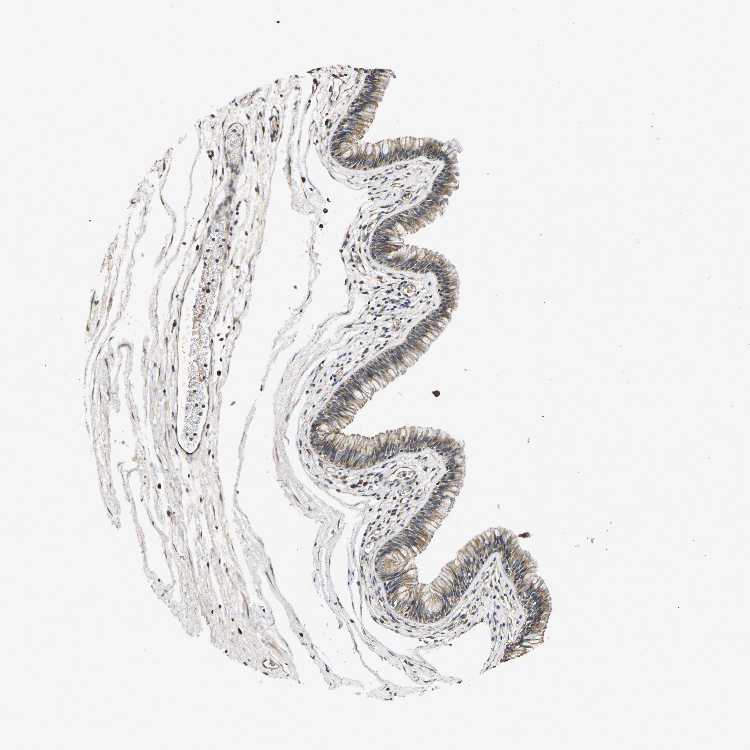

TISSUE PRIMARY DATA NASOPHARYNX Show tissue menu

NASOPHARYNX - Antibody stainingi

Antibody staining in the annotated cell types in the current human tissue is reported as not detected, low, medium, or high, based on conventional immunohistochemistry profiling in selected tissues. This score is based on the combination of the staining intensity and fraction of stained cells.

Each image is clickable and will lead to virtual microscopy that enables deeper exploration of all samples and also displays staining intensity scores, fraction scores and subcellular localization as well as patient and tissue information for each sample.

Antibody HPA015484

Respiratory epithelial cells Medium